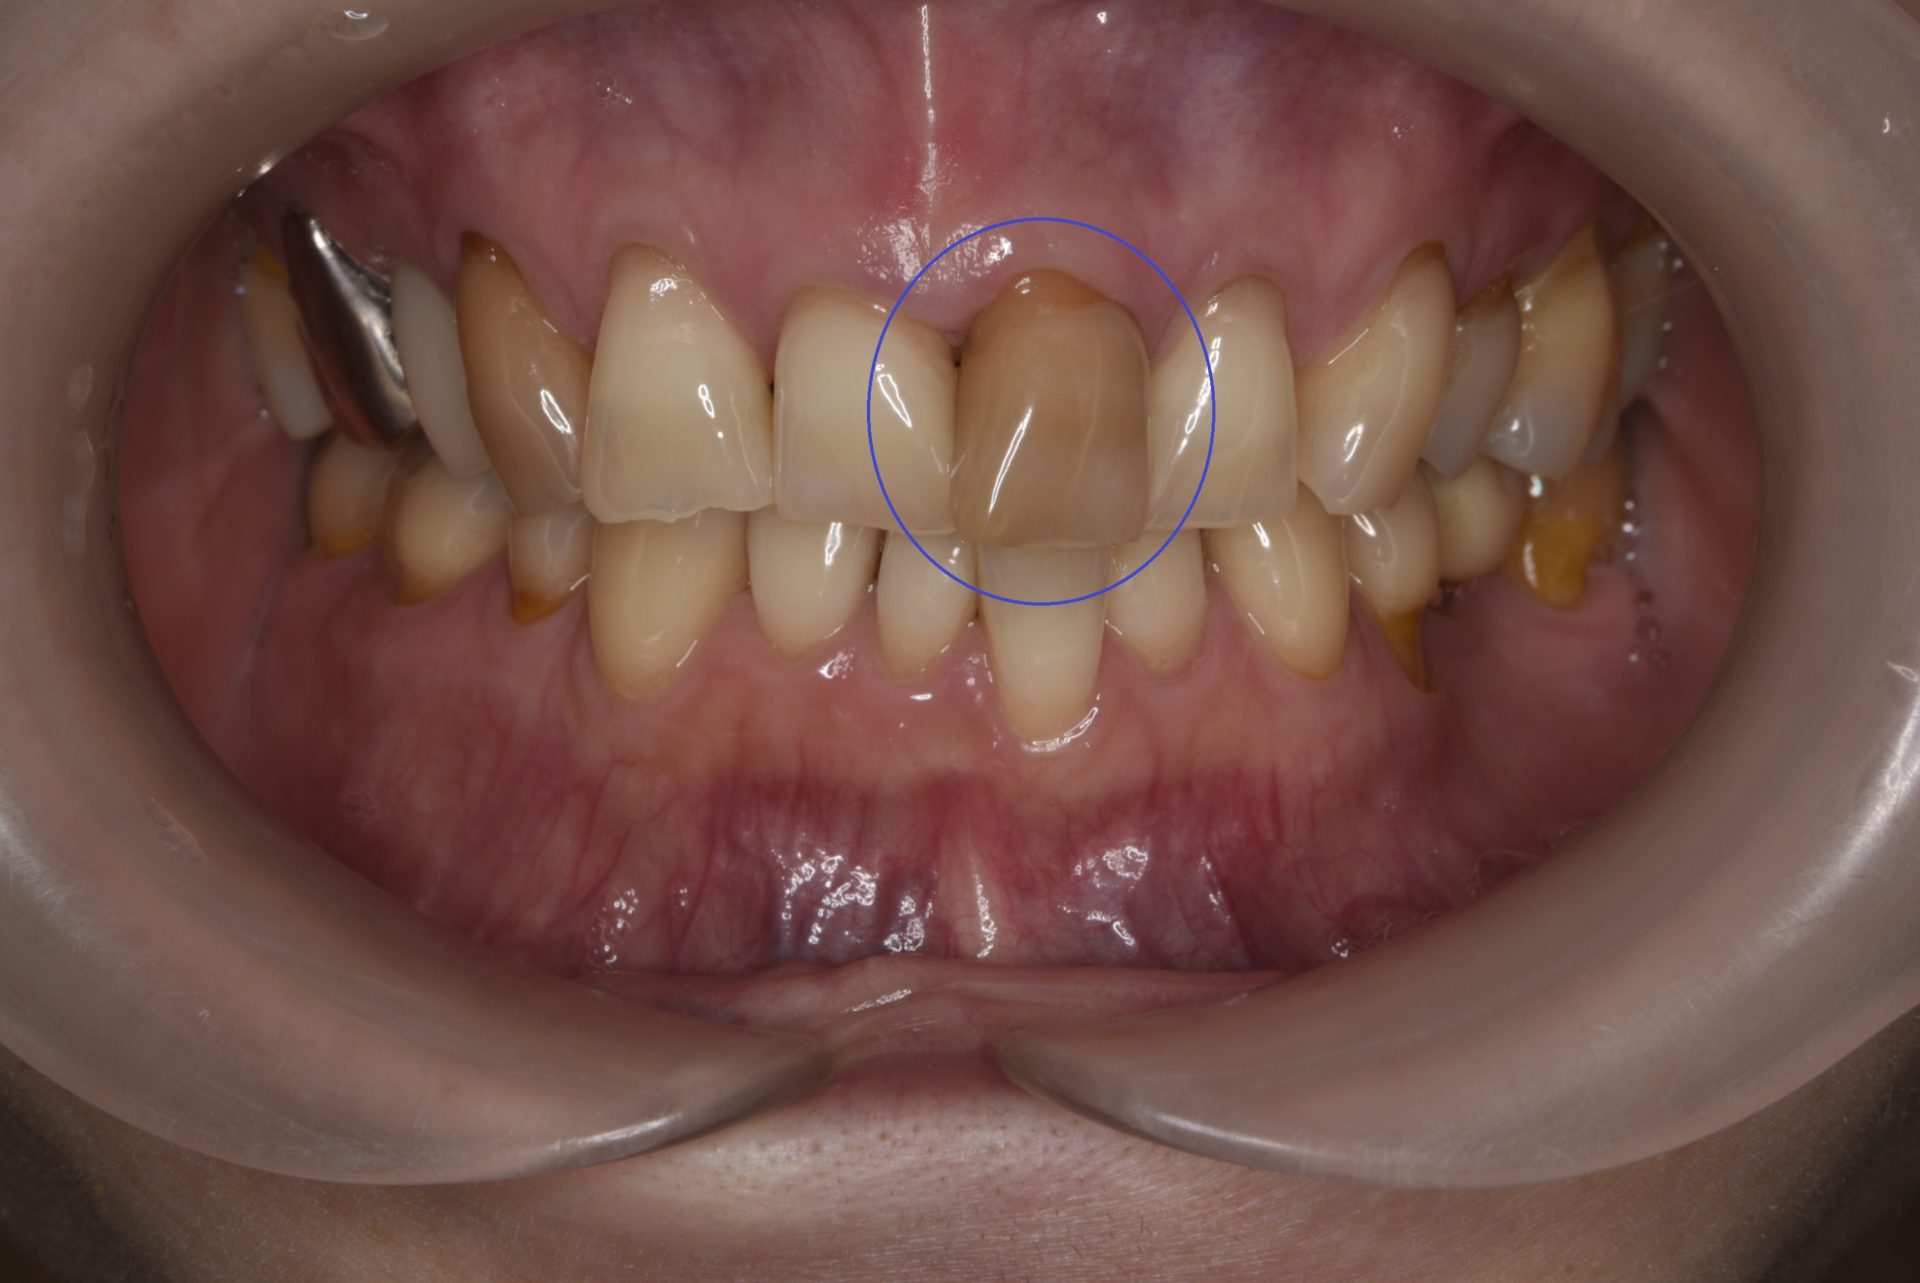

写真の患者さんは〇の歯に痛みがあると来院されました。

審査診断してみると神経が死んでしまっていたので神経を抜く治療をしました。

この時、歯の黄ばみも気になるとの事だったので神経の治療終了後

ウォーキングブリーチもしていきました。